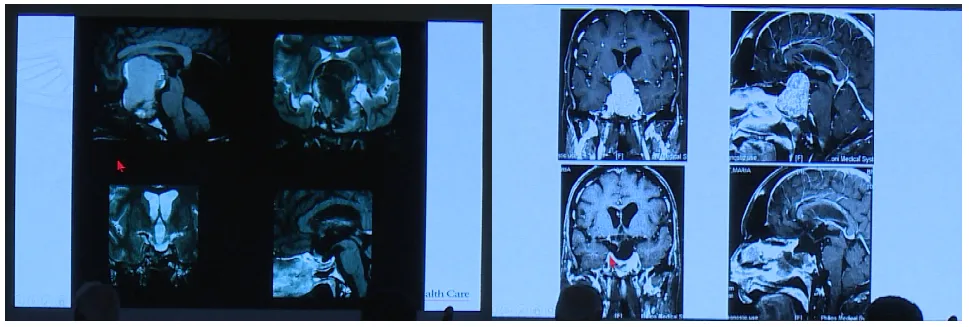

Couldwell教授演讲中展示的部分巨大垂体瘤

目前巨大垂体瘤的主要治疗方式为手术,目的在于最大限度切除肿瘤、改善神经功能障碍以及保留正常垂体功能。巨大垂体腺瘤术前根据影像学及临床表现,个体化选择合适的入路,是成功切除肿瘤的关键。经蝶入路、经颅入路和联合入路是切除肿瘤的可行方法。

垂体瘤从鞍内起源,但是如果肿瘤巨大向颅内突破了鞍隔孔,向颅内广泛地发展,包绕了颅内的血管,特别是大脑中动脉、大脑前动脉、大脑后动脉及其一些重要的细小分支血管。这些血管被包绕,这种情况下通常会选择经颅入路进行肿瘤切除。经颅垂体腺瘤切除术根据垂体瘤生长方向的位置可以分为三种入路途径,经额入路、经硬脑膜外入路和经翼点入路。